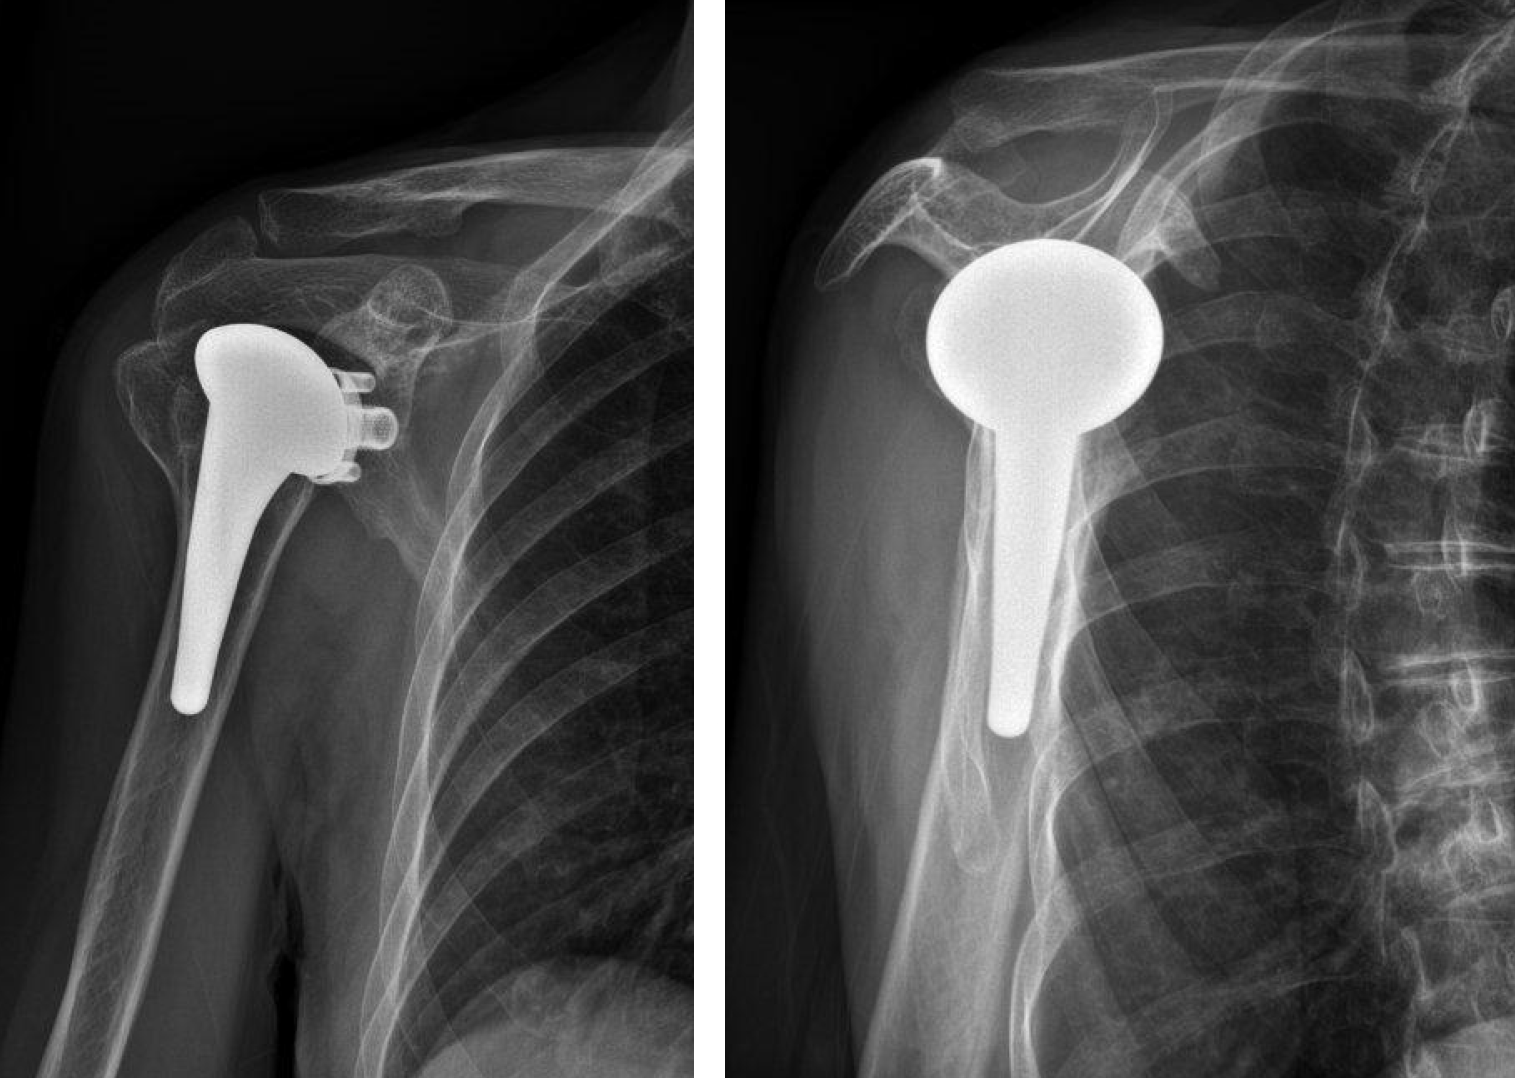

Post-op

Implantation of LINK Embrace using

- Short stem size 15

- Head Adapter 6 mm offset

- Humeral Head with 47 mm diameter, 15 mm height

- Convertible Glenoid size M